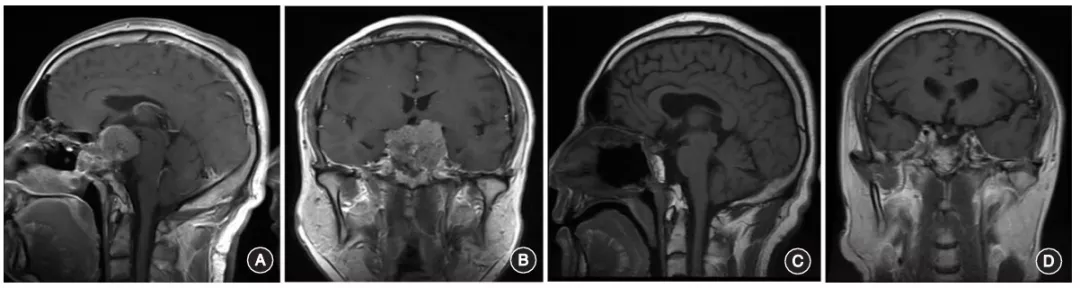

肿瘤两侧为颈内动脉区域,在该区域操作时,应动态使用多普勒超声明确颈内动脉的位置和走行,以避免术中损伤。对于复发颅底硬膜外脊索瘤,肿瘤切除后,尽量保留残存硬膜,以减少术后并发症的发生(图1)。对于已经侵入硬脑膜内的肿瘤或本身就是硬膜内的脊索瘤,肿瘤切除后可清晰显示后方的脑干、基底动脉、视神经等肿瘤背侧结构,此时的颅底缺损应尽量使用带血管蒂的黏膜组织进行重建(图2)。

图2:复发全斜坡脊髓瘤,肿瘤侵入硬脑膜内A,B.术前头颅MRI增强扫描显示肿瘤全部切除,鼻中隔粘膜瓣重建颅底